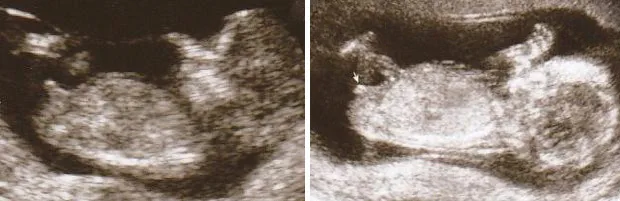

여기에 나타나는 아이의 사진 또한 11 주에서 13 주 사이의 임신 사이에 촬영. 결절이오고있는 것 같습니다 상황 수평으로, 그녀가 소녀임을 나타내는 기둥과 평행하지만 형태 Copogha의 섹스 기관처럼 보입니다. 섹스가 무엇인지 말하기는 어렵습니다.